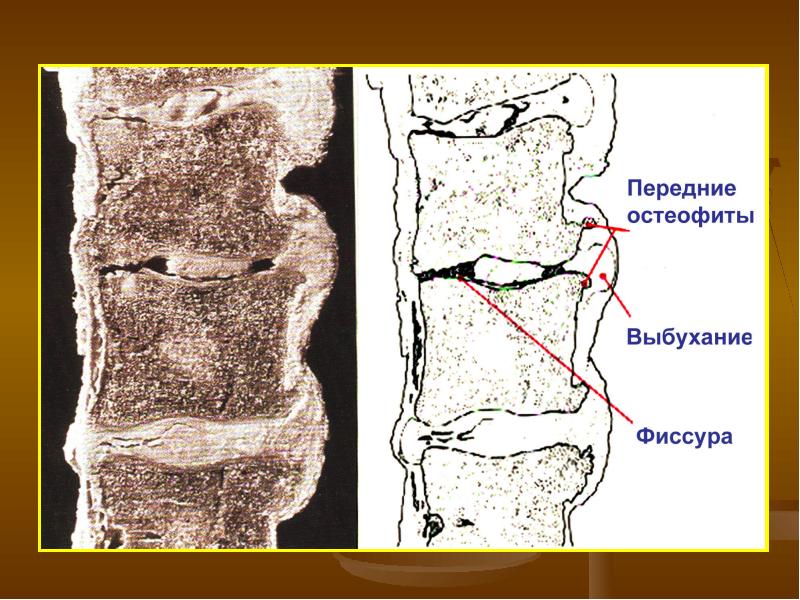

Photos ЧТО ТАКОЕ ОСТЕОФИТЫ